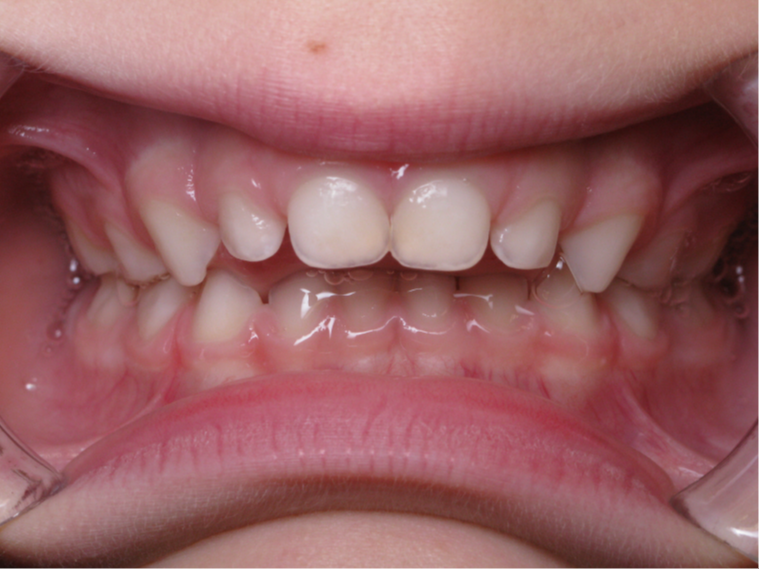

6 décalage sagittal 5 ans

Décalage entre les dents d avant en arrière

bilan début fin de traitement